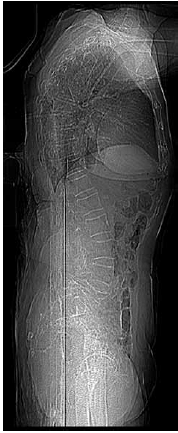

Paciente de 92 anos, de forma súbita e sem causa aparente, iniciou com dor lombar, sem irradiação, que a incomodava para caminhar, sentar e deitar. Sua radiografia de coluna lombar mostrou o seguinte:

(Arquivo pessoal; imagem usada com autorização)

Diante do exposto, assinale a alternativa correta.